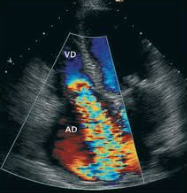

El foramen oval es una apertura natural cuya función es permitir el paso de la sangre oxigenada de la aurícula derecha a la aurícula izquierda durante la vida fetal. Además, gracias a este foramen los nutrientes que llegan a la madre por medio de la placenta y la vena umbilical pueden alcanzar el cerebro y el resto de los órganos fetales. En el momento del nacimiento, los cambios que se producen en la circulación hace que aumente la presión en la aurícula izquierda y por lo tanto se verá favorecido su cierre. En algunas personas, este cierre no se produce y será lo que conocemos como foramen oval permeable.